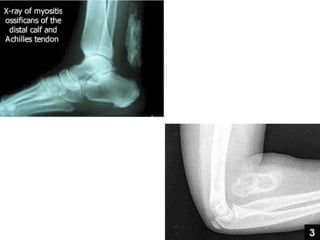

Myositis ossificans

• Myositis ossificans progressiva-

• Very rare congenital progressive disease in which

groups of tendons and muscle, usually around major

joints, become progressively calcified and ossified,

producing severe functional disability.

• Myositis ossificans circumscripta-

• Patients present with lump is muscle.

• History of trauma in only half of the patients.

• Common locations- flexor muscles of the upper arm,

quadriceps femoris, adductor muscle of the thigh,

gluteal muscles and soft tissues of the hand.

• Gross-

• Shell of bony tissue with more or less soft red brown

central area.

• Usually 2-5 cm in diameter and adherent to the

surrounding muscle.

• X ray-

• Periosteal reaction and faint soft tissue calcification

within 3-6 weeks of injury.

• Gradually replaced by mature heterotopic bone by

10-12 weeks.

Myositis ossificans.